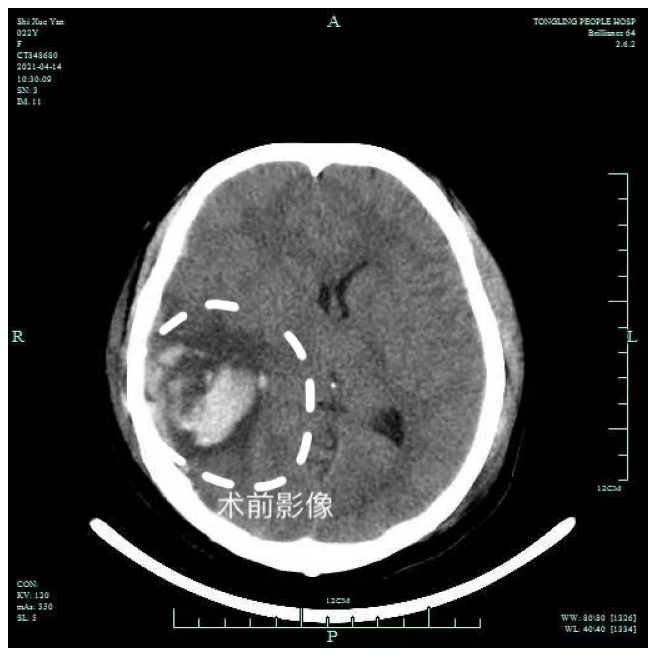

该患者因车祸致伤头部及全身。行头、胸、腹CT检查提示:1、蝶窦内见积液、窦壁见线性骨折,左侧颞骨骨折可能;2、右侧颞内多发脑挫裂伤伴血肿形成,右侧颞内多发脑挫伤伴血肿形成,右侧颞顶颅骨下弧线状血肿,蛛网膜下腔出血;3、左侧锁骨骨折,右侧第6肋骨腋段骨折,骶骨、右侧髌骨、右侧耻骨多发骨折,周围软组织肿胀。我院神经外科以“创伤性脑内血肿”收治入院。

患者意识模糊不清,头面部、全身皮肤多处擦伤,右耳可见血性液流出。入院后给予脱水止血、预防感染等对症治疗。入院五天后,患者意识加深、病情加重,颅内血肿量增多达手术治疗指征。床位医生胡凌向家属充分沟通后,急诊在气管插管全麻下行开颅探查术+脑内血肿清除术+内减压术+去骨瓣减压术。术中仔细清除血凝块及糜烂组织约60ml,患者因处月经期及骨盆骨折,渗血明显,予以小心止血并术中予以输血。术后返回神经外科监护室,在科主任崔明的指导下,予以积极对症治疗。

术后十天,患者意识逐渐清楚,可以用画笔在本子上写爸爸妈妈和自己的想法,能认识亲人,家属非常激动并表示感谢。术后复查CT等检查结果显示脑内血肿已完全清除,病情平稳予以出院行康复治疗。